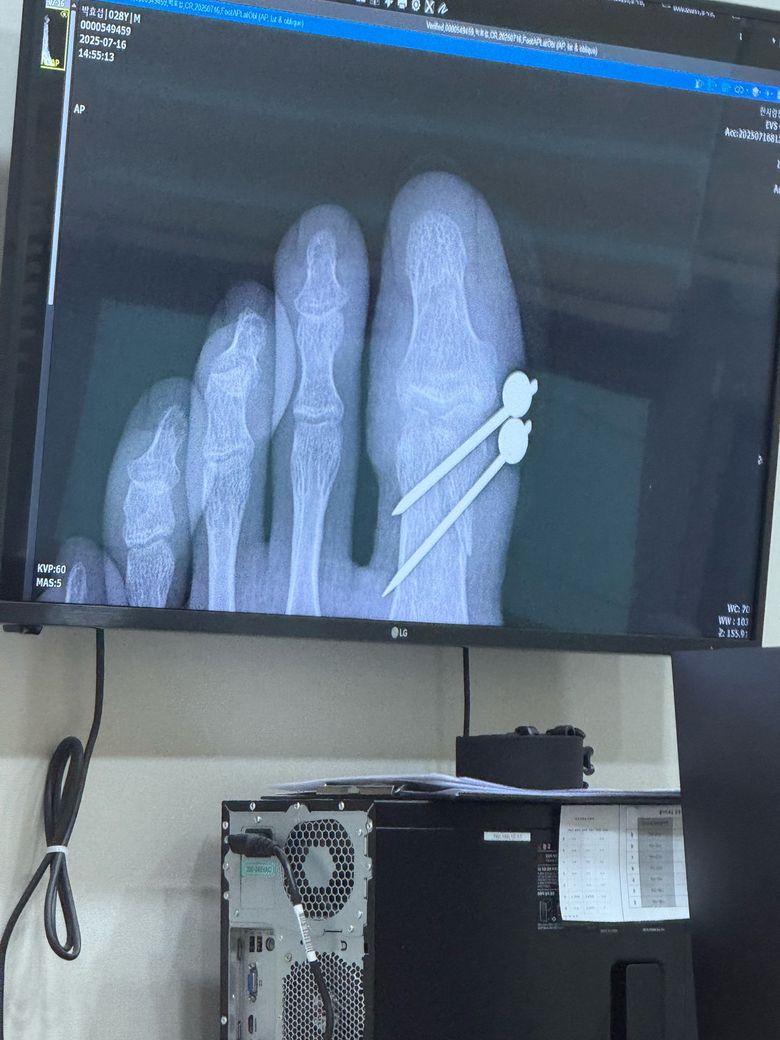

왼쪽 엄지발가락 골절 핀수술5주차 제거

왼쪽 엄지발가락 골절로 인해 핀 수술후

5주차인 현재 핀제거를 하였습니다.

현재 5주차 엑스레이 사진을보니 담당의사선생님 소견으로는 70%~80%가 붙었으며 골절부위 끝쪽인 곳은 삐뚤길래물어보니 어쩔수없다는 식으로 말씀을 해주셨습니다.

1) 혹시 현재 사진으로 보면 70%~80%정도 붙은게 맞을까요?

2) 골절부위 끝쪽 은 저렇게 붙어도 괜찮고 사는데 지장이없을까요? 운동을 하는 직업이라 후유증이 생기면 난감해서요.